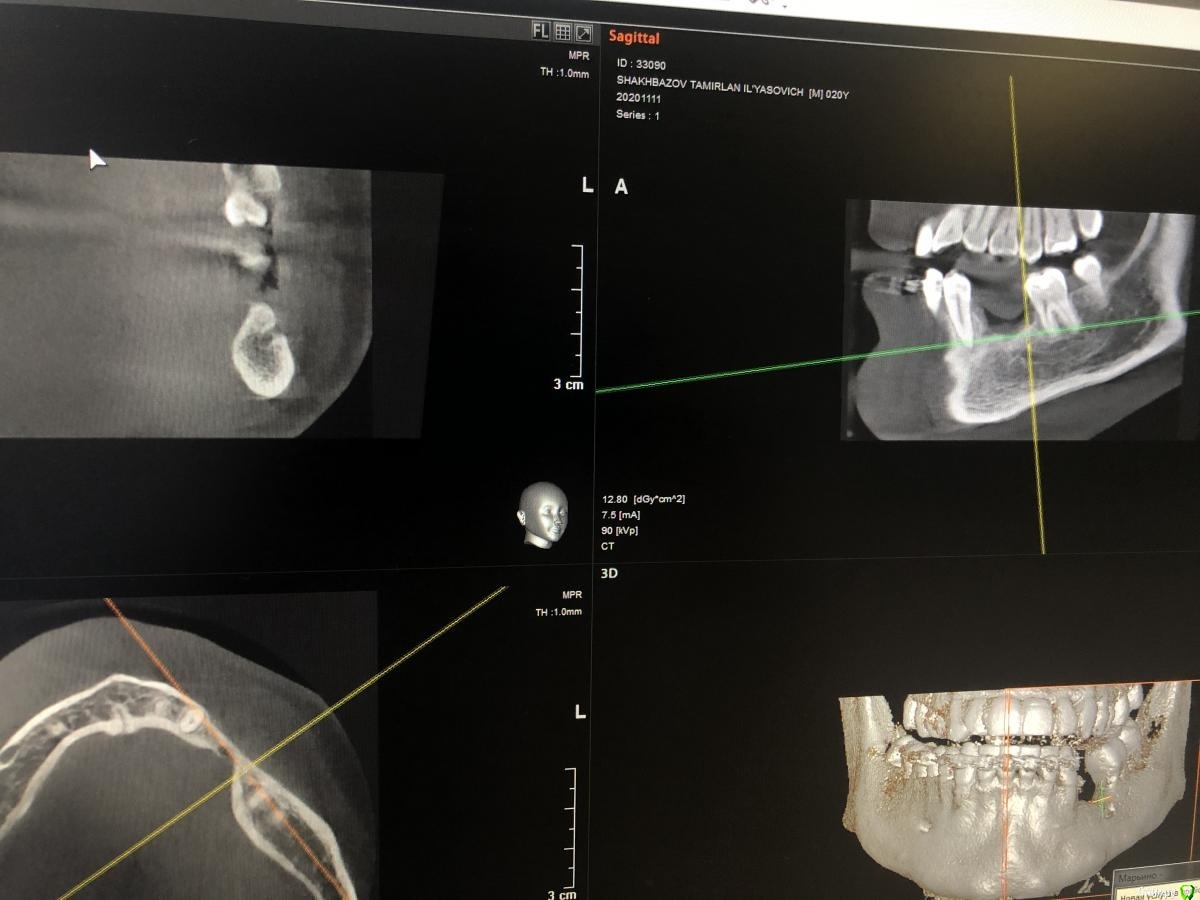

Александр07 Опубликовано 18 ноября, 2020 Поделиться Опубликовано 18 ноября, 2020 Коллеги добрый деньТакой дефект на нч Выход ментального высокоКакой план действий порекомендуетеЕсли ещё срезы нужны скину Ссылка на комментарий

Bier Опубликовано 18 ноября, 2020 Поделиться Опубликовано 18 ноября, 2020 цитопласт. Мобилизация за счет язычного лоскута. Вестибулярный - нужно выделить нерв и тоже можно растянуть довольно сильно. Ссылка на комментарий

Александр07 Опубликовано 19 ноября, 2020 Автор Поделиться Опубликовано 19 ноября, 2020 Вертикалить сеткой или ко Кури. Мобилизацию делать от мукогингивальной границы и язычно в тупую. В чём собственно говоря вопрос?Вопрос был как обойти нерв при нкр) В принципе все понято но решил спросить может кто идею подкинет какую нибудь хорошую) Ссылка на комментарий

АнтонТЛТ Опубликовано 19 ноября, 2020 Поделиться Опубликовано 19 ноября, 2020 Просто выемку вокруг ментального отверстия в каркасе сделать. Ссылка на комментарий